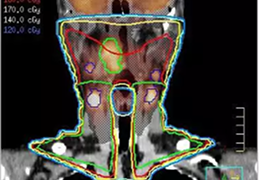

在您进行轮廓勾画以及使用多模图像配准进行 Pinnacle³ 整合治疗计划时,Syntegra能为您带来更强的信心。Syntegra 的多模配准软件能够缩短放射治疗周期,并取得更准确的诊断结果。

Syntegra 能够将生理学影像(如 PET 等)与解剖学影像(如 CT 或 MR)进行自动匹配,使临床医生无需手动调整匹配的影像。

作为飞利浦 Pinnacle³ 放射治疗计划系统的一部分,Syntegra 能够帮助您弥合诊断与治疗之间的鸿沟。例如,放射肿瘤科医生可以将 PET/CT 肿瘤轮廓输入 Pinnacle³ 治疗计划并对其进行回顾,并且可以使用放射科医师已经确定的影像和感兴趣区域。Syntegra 已被归为飞利浦 AcQSim³ CT 模拟软件的一个组成部分。